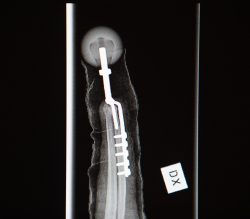

Här är protesen på plats.

Foto: Andreas Hillergren